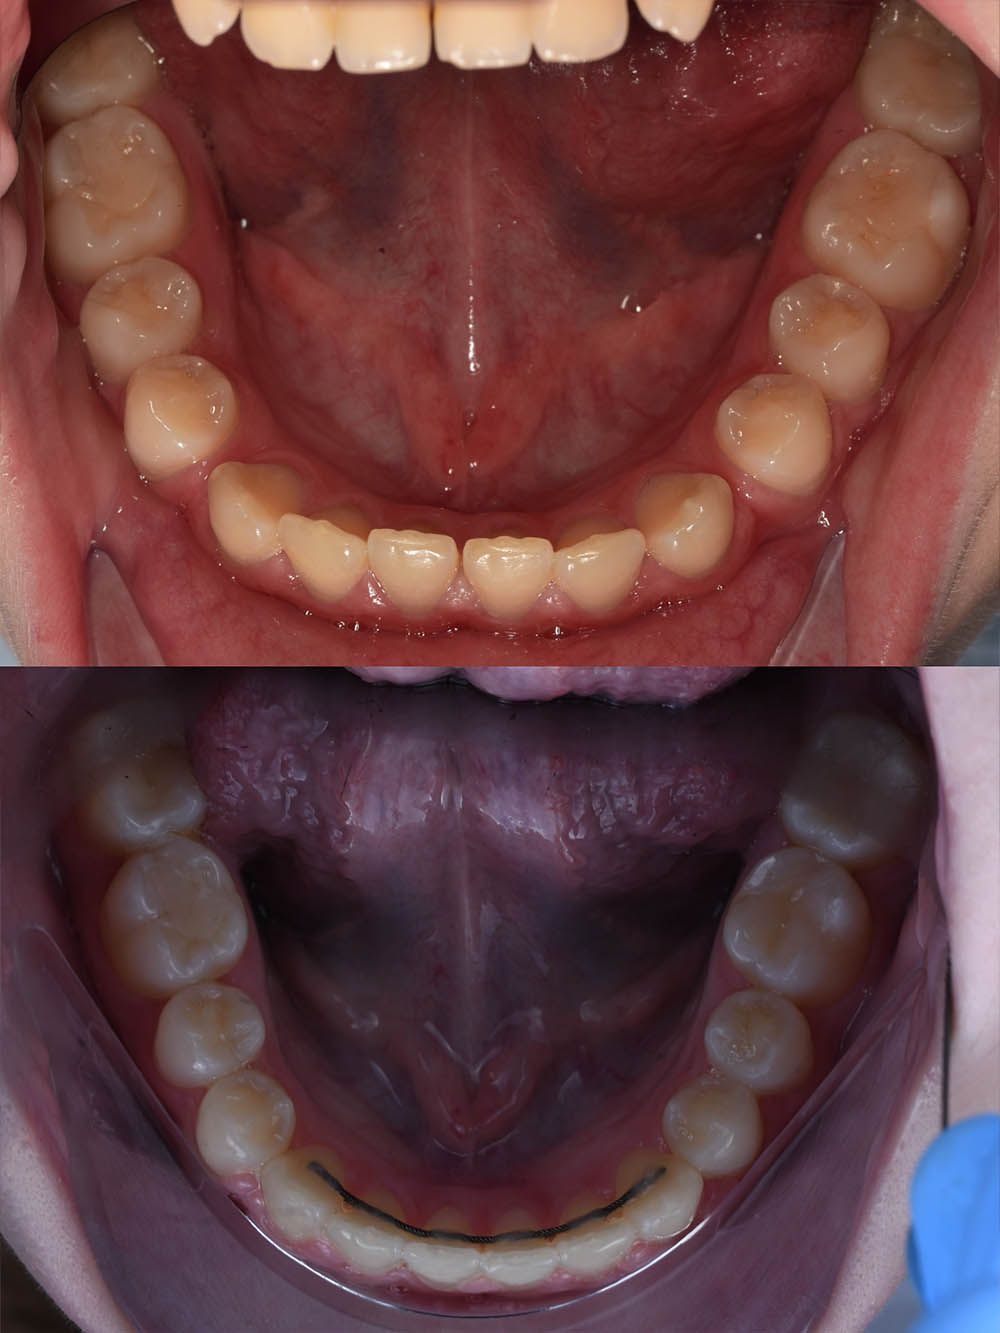

9 месяцев лечения на элайнерах

9 месяцев лечения на элайнерах

9 месяцев лечения на элайнерах